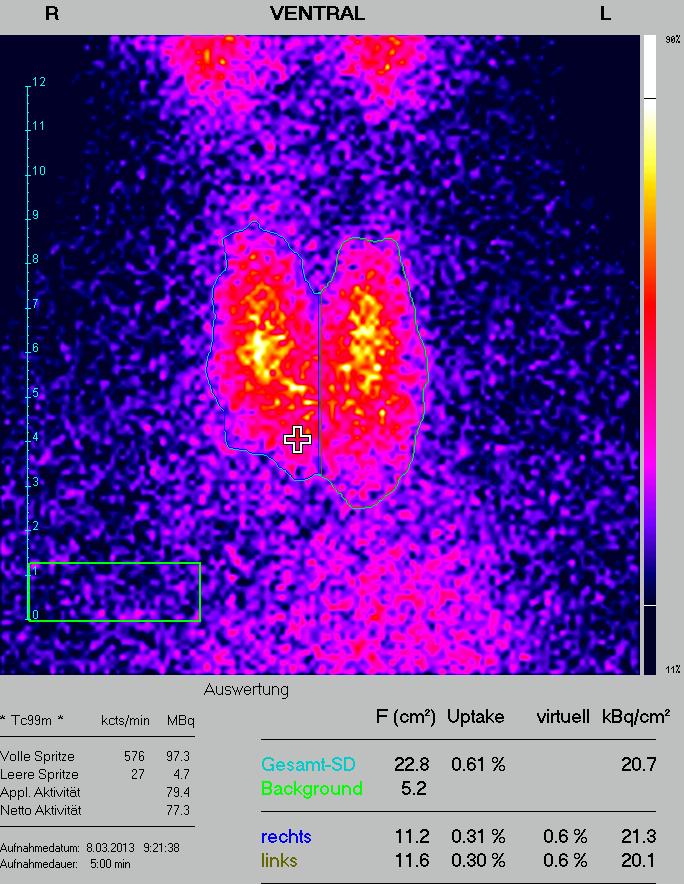

Szintigraphie Schilddrüse : Abbildung 5: Schilddrüse - Szintigraphie / Nach einem entsprechenden zeitraum verteilt sich dieses radionuklid.

Abbildung 5a-b: Schilddrüse - Szintigraphie